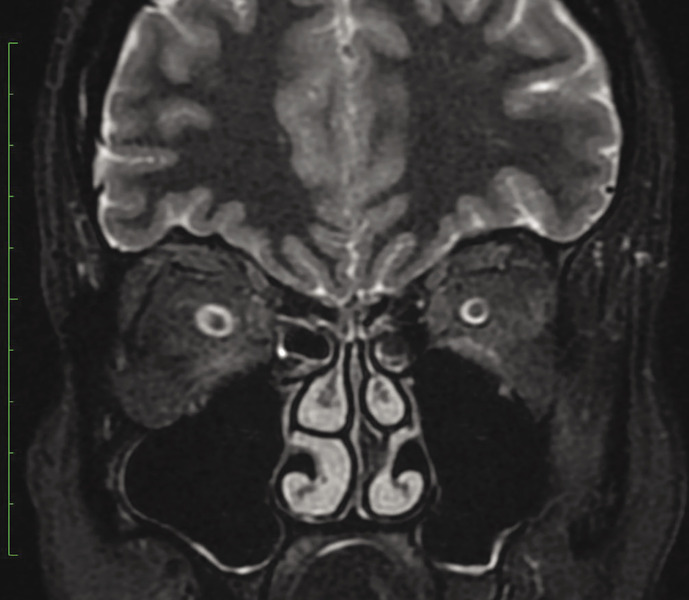

W badaniu neurologicznym wykonanym przy przyjęciu na oddział nie stwierdzono odchyleń od stanu prawidłowego, poza zgłaszanym przez pacjentkę dwojeniem przy spojrzeniu na wprost i w prawo. Wykonano rezonans magnetyczny (MR) głowy z kontrastem, który wykazał objaw częściowo pustego siodła tureckiego (ryc. 1). W MR odcinka szyjnego kręgosłupa uwidoczniono cechy umiarkowanej spondylozy szyjnej, bez zmian pourazowych. W rezonansie magnetycznym oczodołów wykazano natomiast cechy nadciśnienia śródczaszkowego pod postacią zwiększonej ilości płynu w pochewkach nerwów wzrokowych oraz obrzęku tarcz, z poszerzeniem zbiornika nadsiodłowego (ryc. 2, 3).

Rycina 2. Rezonans magnetyczny oczodołów STIR w płaszczyznach czołowych – zwiększona ilość płynu w pochewkach nerwów wzrokowych